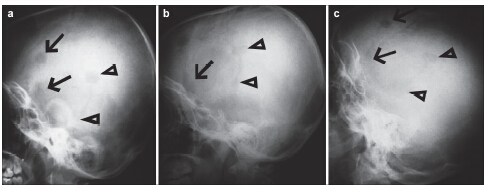

摘要 Objectives: In this case report, we describe the design, fabrication and clinical outcomes of a novel bioresorbable, mineralized collagen burr-hole plug for the reconstruction of craniotomy burr-holes.

Methods: Mineralized collagen burr-hole plugs were fabricated via a biomimetic mineralization process. The biomimetic mineralized collagen has a similar chemical composition and microstructure to natural bone tissue, thereby possessing good biocompatibility and osteoconductivity. The mineralized collagen burr-hole plugs were implanted into three patients, and clinical outcomes were evaluated at one-year follow-ups.

Results: All bone defects healed very well using the mineralized collagen burr-hole plugs, and there were no adverse reactions at the surgical sites.

Conclusions: The clinical outcomes indicated that the mineralized collagen was effective for reconstructing burr-holes in the skull after craniotomy.

Abstract: Objectives: In this case report, we describe the design, fabrication and clinical outcomes of a novel bioresorbable, mineralized collagen burr-hole plug for the reconstruction of craniotomy burr-holes.